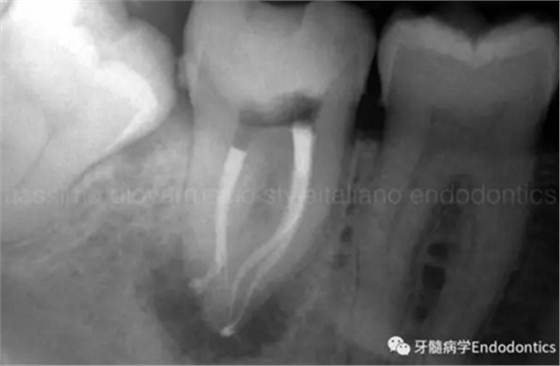

圖11.術(shù)后X片顯示完成了根管的三維充填并很好地保留了復(fù)雜的解剖形態(tài)結(jié)構(gòu)。

圖12.對(duì)于較為困難的病例,探查根管時(shí)可能需要很多嘗試。一旦銼的尖部繞過(guò)了阻礙,會(huì)深入根管。

圖13.在探查的過(guò)程中,銼的硅膠止片的方向可以提示醫(yī)師銼尖越過(guò)障礙時(shí)彎曲的方向,即描述了通路的方向。扭動(dòng)銼使其進(jìn)入的更深,使用根尖定位儀檢查,直到到達(dá)全長(zhǎng)。

圖14.一旦通過(guò)了障礙,應(yīng)避免將銼退出至障礙水平,因?yàn)殇S會(huì)不可避免的被拉直,之后除非將銼完全退出,重新預(yù)彎,重新插入,否則無(wú)法通過(guò)障礙。在S形彎曲根管內(nèi),存在兩處障礙,當(dāng)銼繞過(guò)根管內(nèi)第一處障礙后會(huì)在第二個(gè)彎處再次遇到根尖方向的阻力。在這樣的病例中,將銼稍微回退少許,旋轉(zhuǎn)180度,輕輕扭動(dòng),觀察銼是否能到達(dá)全長(zhǎng)。